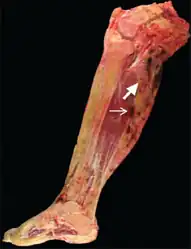

Per Nature, malignant Tenosynovial giant cell tumor tend to be "large, fleshy, and poorly circumscribed with areas of hemorrhage and necrosis" , while small histiocytes, larger mononuclear cells, siderophages were the given, histiologically.[11]

55-year-old female who initially presented with progressive right posterior calf pain now status post right leg amputation for malignant tenosynovial giant cell tumor. Gross pathology of the amputated right lower extremity reveals a heterogeneous tumor with cystic (thick arrow) and solid (thin arrow) components extending from the popliteal fossa to the mid-calf. -